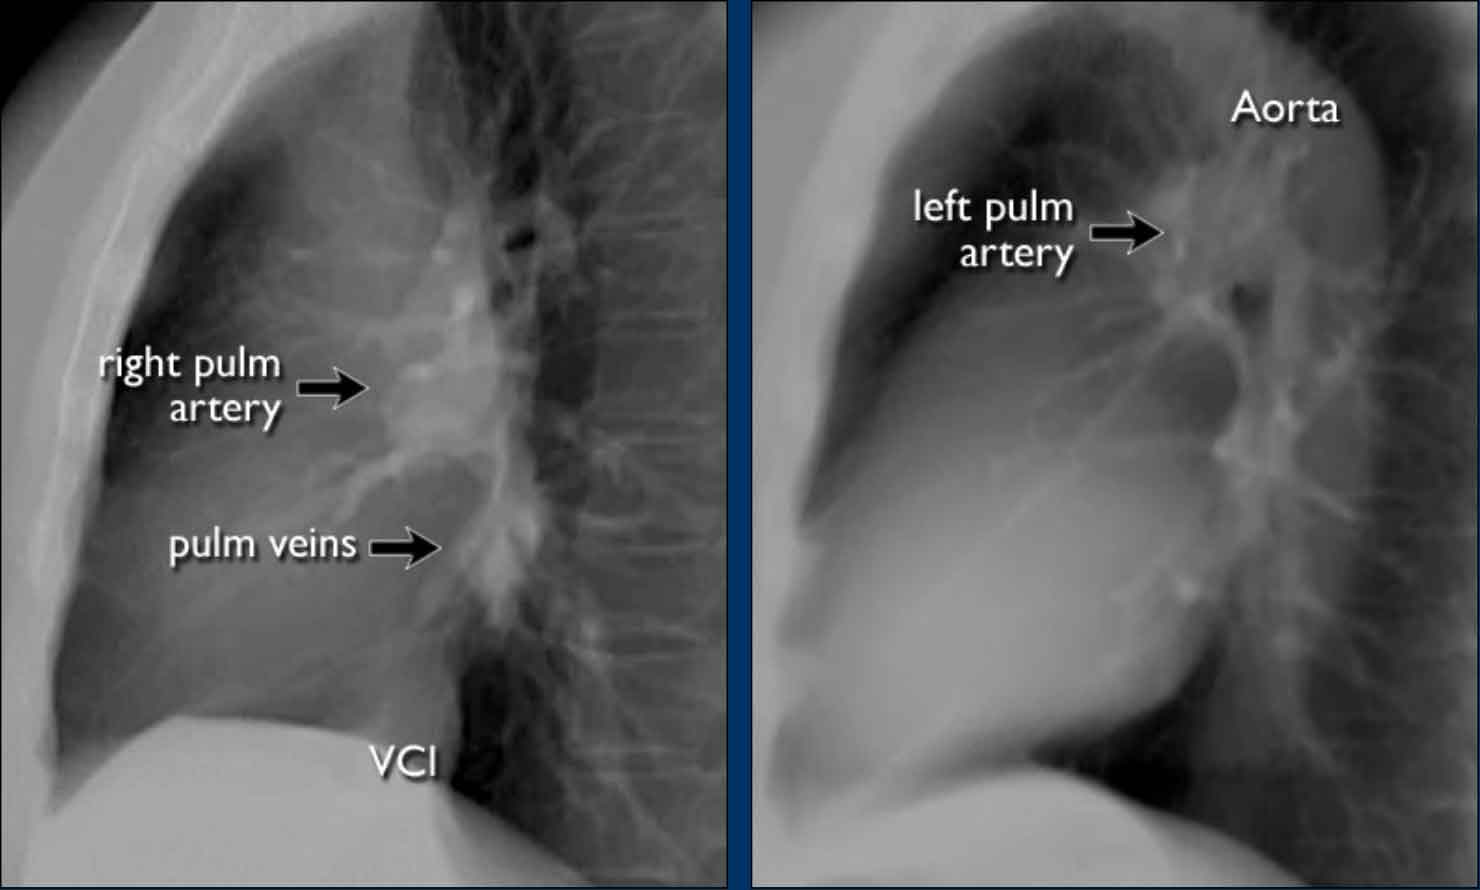

Pulmonary Vasculature and Hilar Structures

The left pulmonary artery (shown in purple) arches above the left main bronchus and is situated higher than the right pulmonary artery (in blue), which courses anterior to the right main bronchus.

Understanding normal hilar anatomy on the lateral view facilitates detection of abnormalities.

For example:

• On the PA view, hilar enlargement may be noted, but it can be difficult to differentiate between vascular dilatation and lymphadenopathy.

• On the lateral view, the presence of rounded opacities in regions where pulmonary vessels are not normally seen strongly suggests enlarged lymph nodes.

Hili

The normal hilar shadow on chest radiography is predominantly vascular in nature—comprising approximately 99% of pulmonary arteries and, to a lesser extent, pulmonary veins (1).

These vascular structures have well-defined, smooth margins and demonstrate normal branching patterns.

An important anatomical consideration is that the left hilum is normally situated higher than the right.

This relationship arises from the course of the pulmonary arteries: the left pulmonary artery arches over the left main bronchus, while the right pulmonary artery courses anterior to the right main bronchus, which is typically positioned lower than its left counterpart.

In a minority of cases, the hila may be at the same level, but the right hilum should never be higher than the left.

On lateral chest radiographs, both pulmonary arteries and veins are identifiable and should not be misinterpreted as lymphadenopathy. Occasionally, pulmonary veins may appear prominent.

The left main pulmonary artery passes superior to the left main bronchus and lies higher than the right pulmonary artery, which courses anterior to the right main bronchus.

The included images are thick-slab sagittal CT reconstructions of the thorax, which enhance visualization of hilar structures.

The lower lobe pulmonary arteries descend from the hilum in a vertically oriented fashion.

Radiographically, these vessels are colloquially referred to as the “little finger” due to their size and shape, approximating that of a little finger (1).

On PA chest radiographs, the "little finger" of the right lower lobe pulmonary artery is visible in approximately 94% of normal individuals, while on the left side it is visible in about 62% (1).